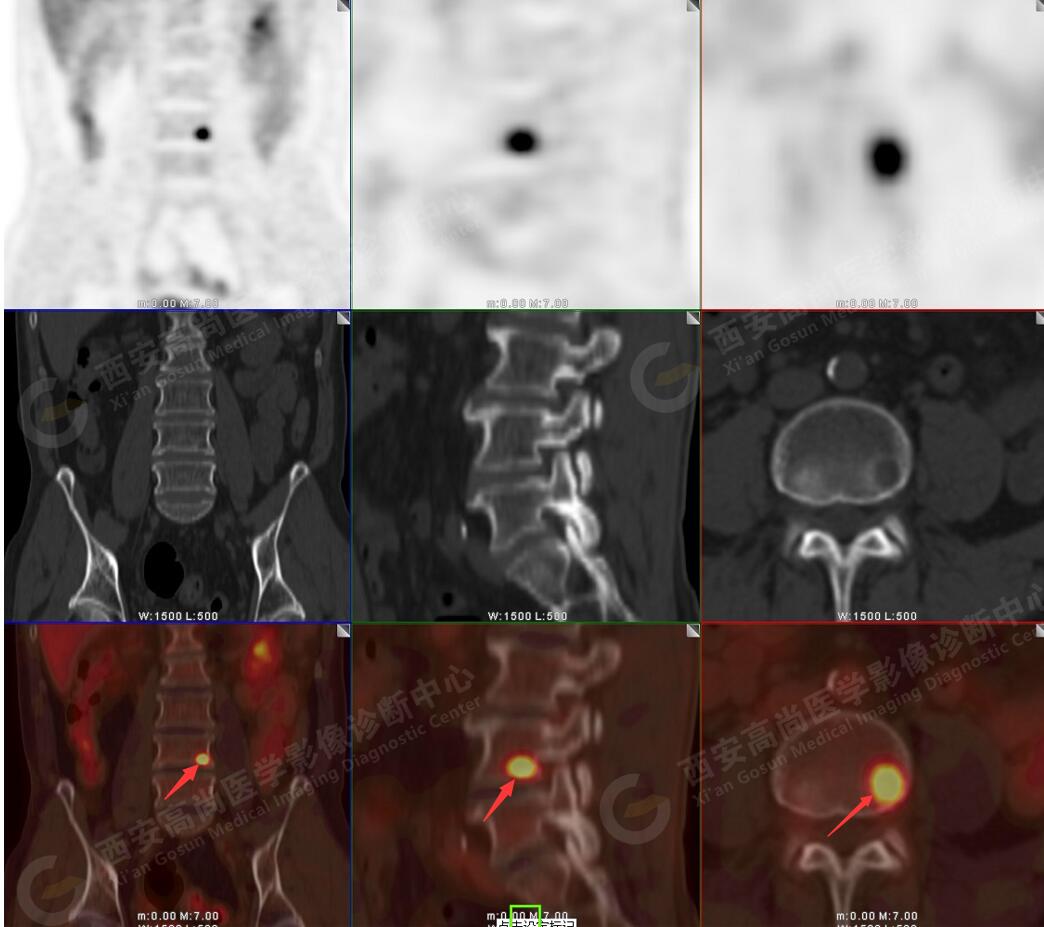

5.腰4椎體左側(cè)緣溶骨性骨質(zhì)破壞,F(xiàn)DG代謝異常增高,考慮骨轉(zhuǎn)移瘤。

以上病變符合:T4N3M1c,ⅣB期(UICC/AJCC,2018年第8版肺癌TNM分期)。